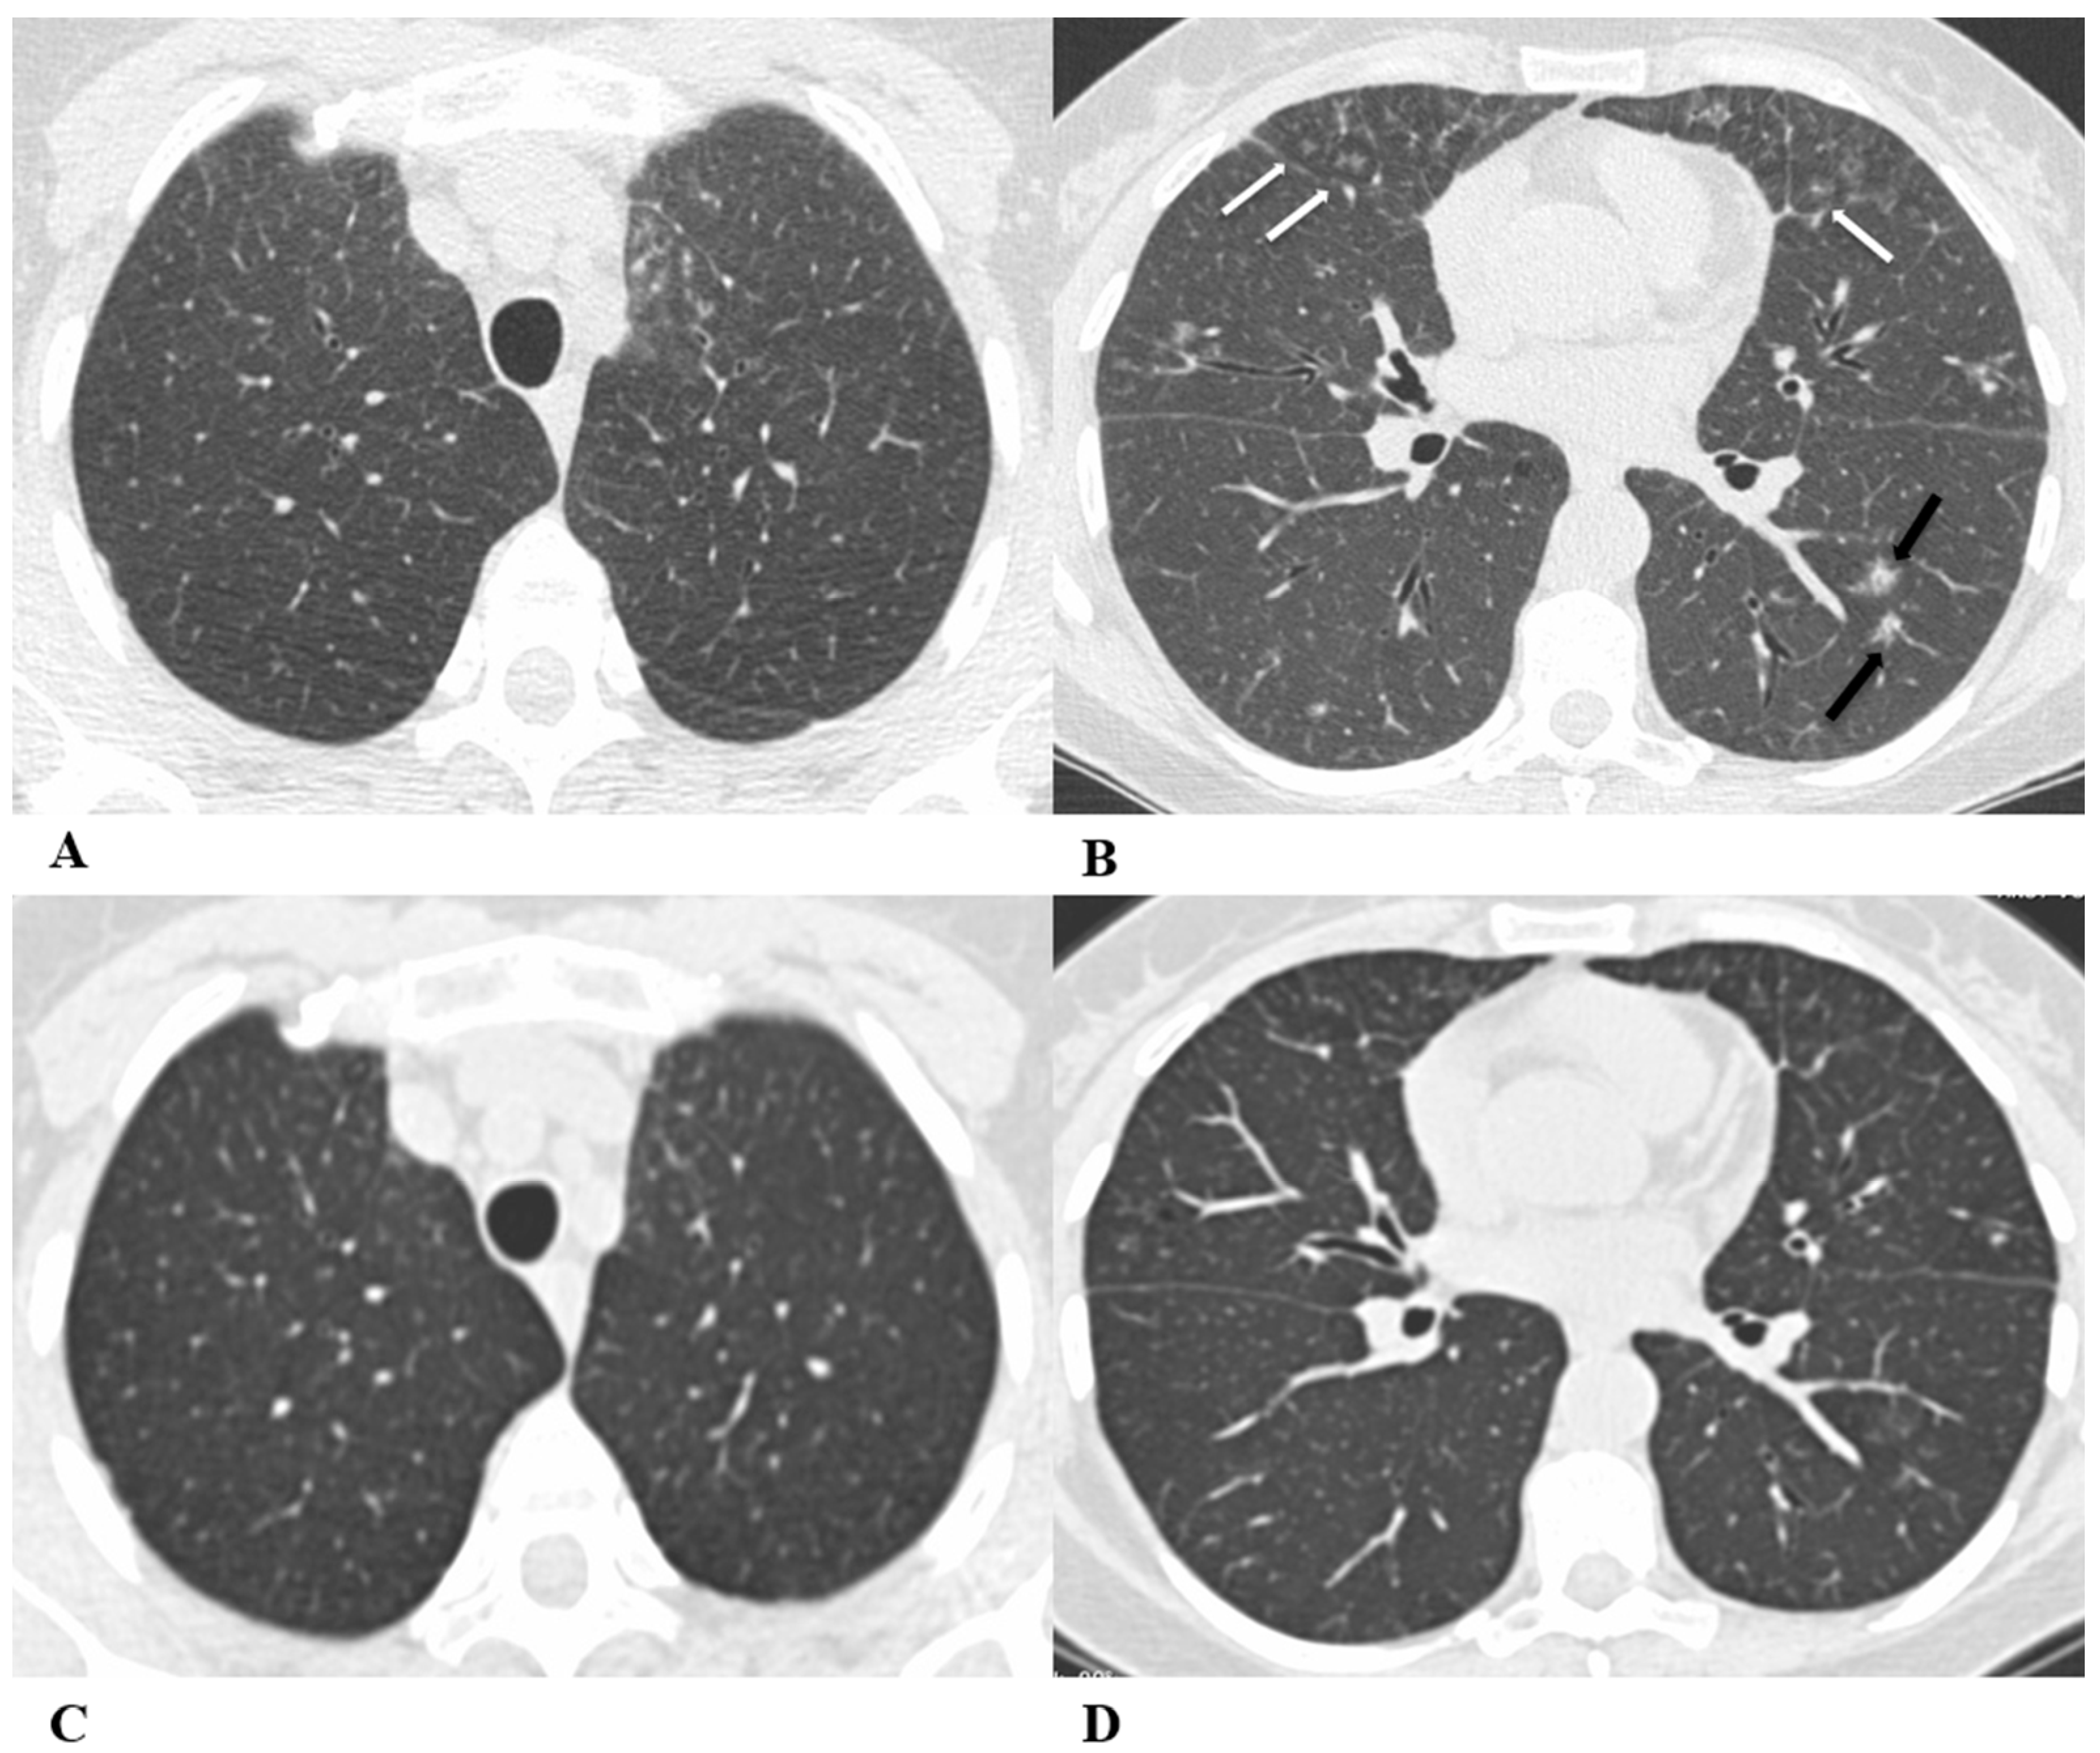

Figure 1.

Organizing pneumonia (OP). Organizing pneumonia is determined by the presence of granulation tissue buds in the alveoli, alveolar ducts and distal bronchioles. On HRCT, OP is characterized by diffuse and bilateral areas of consolidation and ground-glass opacities (GGOs), often migratory, with predominantly peripheral/subpleural and peribronchovascular distribution [9,12]. Other OP findings are the “reversed halo sign” (a focal area of GGO surrounded by a ring of denser air-space consolidation; if the surrounding ring is incomplete, it is mentioned as the “atoll sign” [16]) and, rarely, centrilobular nodules.

(A–D) A 64-year-old man with a diagnosis of small-cell lung cancer with adrenal and brain metastases, treated with nivolumab. Six months after beginning immunotherapy, the patient presented progressive dyspnea and dry cough. Chest auscultation revealed diffuse crackles associated with a moderately restrictive functional pattern. The blood count did not show significant leukocytosis but showed increased inflammatory indexes. The patient benefited from a temporary suspension of immunological therapy with steroid intake, but the subsequent relapse forced a radical change in therapeutic strategy.

Axial chest CT images (A–D) show bilateral confluent areas of GGOs and peripheral and peribronchovascular consolidative opacities.

The structural alteration of the right pulmonary hilum due to the presence of neoplastic tissue, with the infiltration of the ipsilateral main bronchus (A) and the “reversed halo sign” (white arrow (D)), are also visible.